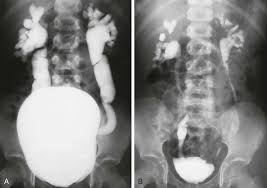

Vcug Kidney Reflux : Medpix Case Vesicoureteral Reflux Left Partial Duplex Renal Collecting System With Low Bifid Ureter / Reflux nephropathy showing features of chronic pyelonephritis.. Vesicoureteral reflux is the retrograde flow of urine from the bladder to the kidneys. Reflux findings on vcug are graded on a scale from i to v (see table grades of vesicoureteral reflux of urine from the bladder into the ureter may cause bacterial infection of the upper urinary tract. Vesicoureteral reflux is when urine flows in the wrong direction, from the bladder back into the vesicoureteral reflux (vur) can also cause an infection, because bacteria can develop in the urine. Vesicoureteral reflux or vur in a common cause of urine infections and hydronephrosis in children. Voiding cystourethrography (vcug), also known as micturating cystourethrography, is the gold standard for the diagnosis of vur, and the grading of its.

Urine refluxes into ureter and kidney and causes significant dilation with twisting of the ureter. This is a particular risk if. What are the symptoms and complications of vesicoureteral reflux? The tests they do to test for kidney reflux. I am a female, 22 yrs old and i was born with kidney reflux in both kidneys.

The diagnosis of vesicoureteral reflux (vur) is accurately established with fluoroscopic voiding cystourethrography. Vesicoureteral reflux (vur), also known as vesicoureteric reflux, is a condition in which urine flows retrograde, or backward, from the bladder into one or both ureters and then to the renal calyx or kidneys. Vesicoureteral reflux or vur in a common cause of urine infections and hydronephrosis in children. What to expect during a vcug: What is vesicoureteral reflux (vur)? The clinical significance of vur has been based on. Reflux nephropathy showing features of chronic pyelonephritis. Kidney damage occurs in some people with reflux. Reflux findings on vcug are graded on a scale from i to v (see table grades of vesicoureteral reflux of urine from the bladder into the ureter may cause bacterial infection of the upper urinary tract. Are they able to give the child anything to help them relax a little? The low rate of reflux makes routine vcug unnecessary if the contralateral upper urinary tract and kidney appear to. Insights from the chronic kidney disease in children (ckid) study lim r. The tests they do to test for kidney reflux.

Vur can increase the risk of a kidney uti (also called pyelonephritis). Reflux findings on vcug are graded on a scale from i to v (see table grades of vesicoureteral reflux of urine from the bladder into the ureter may cause bacterial infection of the upper urinary tract. The kidneys produce urine, which travels down tubes called the ureters. Hey guys today is the second day of tests for my son's kidney reflux. This is a particular risk if. Reflux nephropathy showing features of chronic pyelonephritis. Kidney reflux doesn't have symptoms, but urinary tract infections do. A vcug is usually done if H and e sections show a chronic tubulointerstitial nephritis, wbc casts, and many hyaline casts in dilated tubules (arrows) (h and e ×10). Vur can increase the risk of a kidney uti (also called pyelonephritis). What is vesicoureteral reflux (vur)? This is called vesicoureteral reflux or vur. The vcug looked great and i was feeling fine.